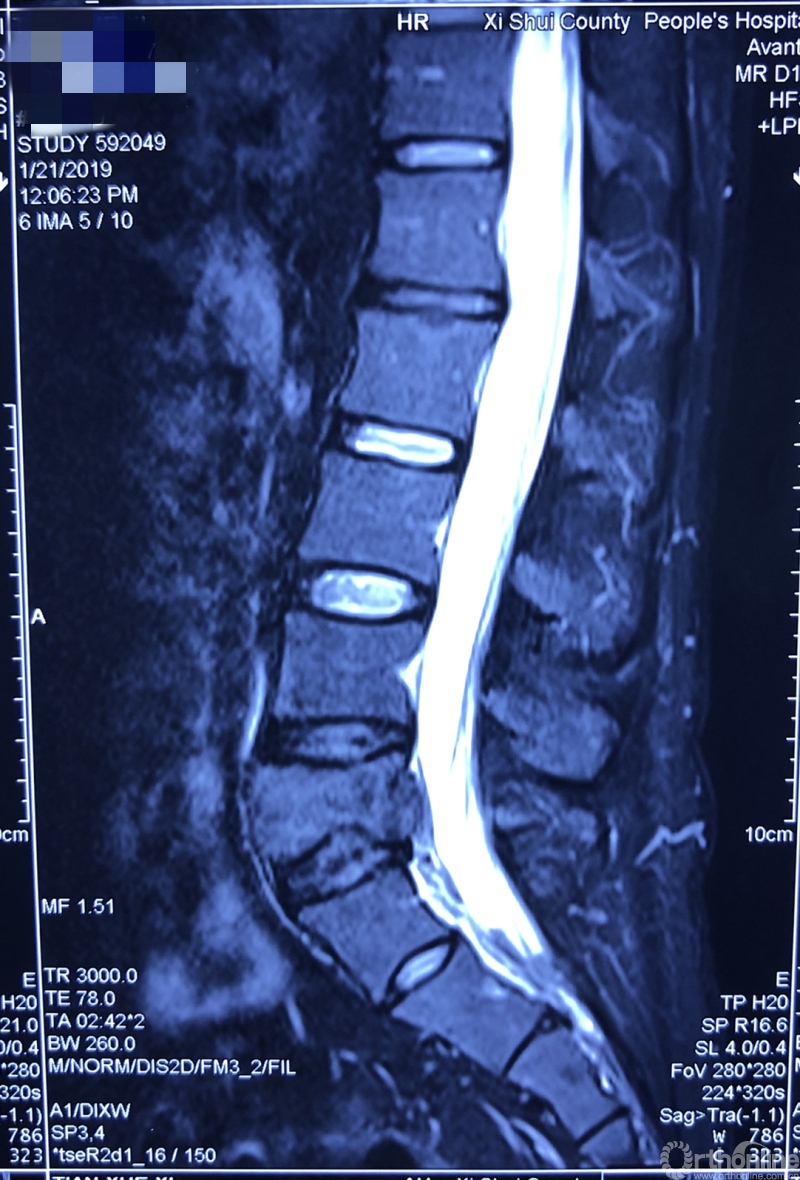

据介绍,患者为39岁男性,在一年前开始出现腰部反复疼痛的症状,休息下后疼痛还可以缓解,当时并未引起患者重视。过年后感觉疼痛加重,赴当地医院检查。核磁共振显示腰椎上长了一个鹅蛋大小的肿瘤,不偏不倚地侵蚀在第五节腰椎上,正是腰椎和骨盆连接部位附近。于是患者来同济医院骨科就诊。

就诊前CT

通过对患者详细的身体检查、穿刺活检和综合评估后,确诊患者是腰椎骨巨细胞瘤,第五腰椎破坏70%以上,邻近软组织也有破坏。这种肿瘤属于交界性的有恶性倾向的良性肿瘤,若不彻底切除,患者疼痛会逐渐加剧,甚至因骨质坍塌而瘫痪,若肿瘤细胞转移更会危及生命。若是能在早期尽快彻底、完全地切除肿瘤及被侵蚀椎体,病人才很可能完全战胜肿瘤。